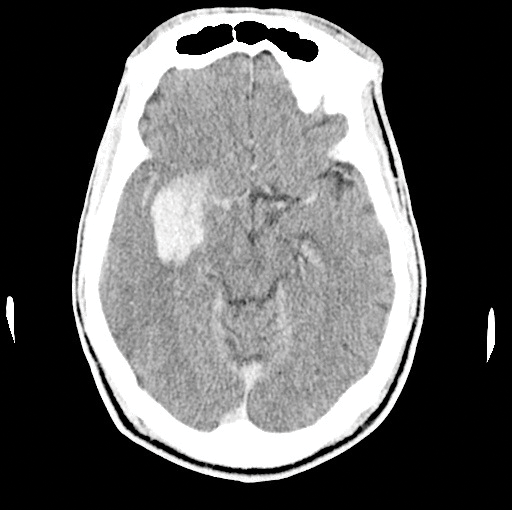

On your next shift, you find yourself evaluating a 58-year-old-male with acute onset of left upper and lower extremity weakness and a facial droop that started 2 hours ago. Naturally you get a CT, which shows no bleeding, but displays a dense right MCA (Image 1). With the patient's significant deficits, you decide to unsheathe the double-edged sword of tissue plasminogen activator (tPA). About an hour into treatment, the patient becomes significantly less responsive. A repeat CT shows the most feared complication of tPA: an intracerebral hemorrhage (ICH) (Image 2). Now what do you do? Call the chaplain? Is there anything else we can do to reverse the effects of tPA?